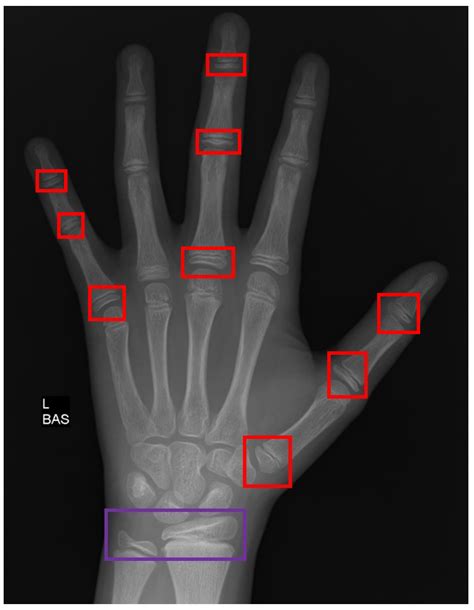

Interpreting Hand X Ray results requires a trained eye. Radiologists and orthopedic specialists are typically responsible for analyzing the images. Key areas of focus include:

• Bone Density: Variations in bone density can indicate fractures, tumors, or other abnormalities.

• Joint Spaces: Narrowing of joint spaces can be a sign of arthritis.

• Soft Tissue: While X-rays primarily focus on bones, they can also provide some information about soft tissues, such as swelling or the presence of foreign bodies.

Here is a table outlining some common findings and their potential diagnoses:

Finding Potential Diagnosis

Fracture Line Bone Fracture

Joint Space Narrowing Arthritis

Bone Lesion Tumor or Cyst

Soft Tissue Swelling Infection or Injury